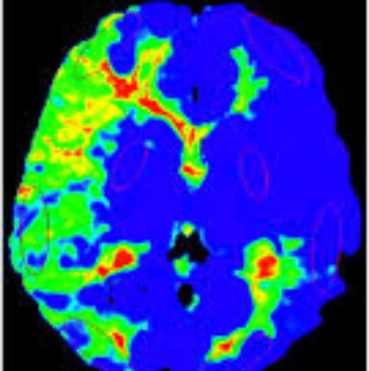

Special studies: MR Perfusion imaging

Diagnosis is made using imaging studies such as MRI, MR Angiography, CT scans, and cerebral angiography, which evaluate blood flow and detect narrowing of brain vessels with formation of collaterals appearing as ‘Puff Of Smoke’. Special MRI scans are used to understand the blood flow to the brain.